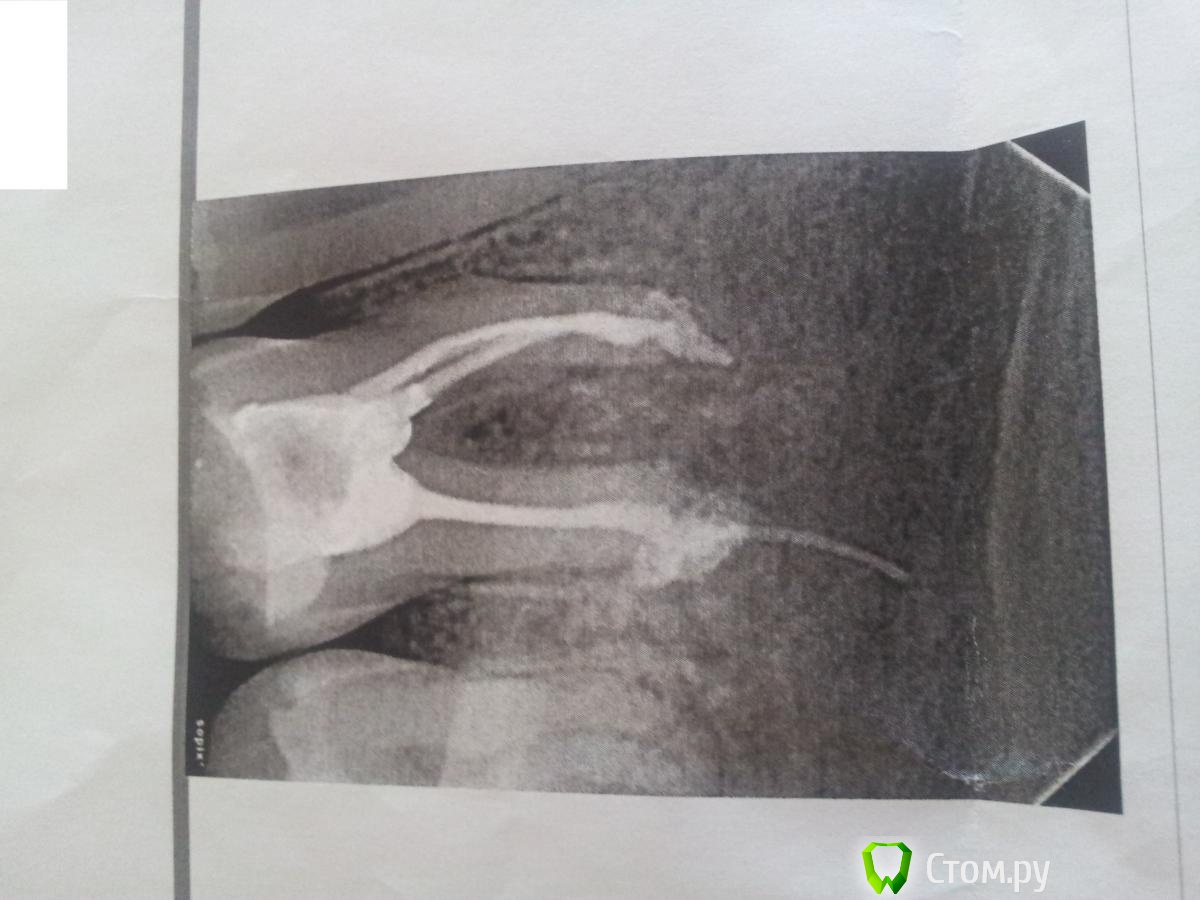

Жамал Опубликовано 2 сентября, 2014 Поделиться Опубликовано 2 сентября, 2014 Я лечила периодонтит 6-го нижнего зуба, 2 дня назад сделали пломбировку каналов, ноющие боли, ночью не сплю, спасаюсь кетоналом (еще кормлю)((.Сегодня сделала рентген одна пломба вышла за пределы канала, врач говорит что при лечении периодонтита специально так делают.посмотрите снимок и оцените пожалуйста Ссылка на комментарий

Bier Опубликовано 2 сентября, 2014 Поделиться Опубликовано 2 сентября, 2014 Специально так делать не нужно 2 Ссылка на комментарий

Bier Опубликовано 2 сентября, 2014 Поделиться Опубликовано 2 сентября, 2014 Оставить, вынуть лишнее можно только хирургически или не вынимать 1 Ссылка на комментарий

anvladd Опубликовано 2 сентября, 2014 Поделиться Опубликовано 2 сентября, 2014 Лишканули конечно, какой материал в каналах,в выписке посмотрите? Ссылка на комментарий

anvladd Опубликовано 2 сентября, 2014 Поделиться Опубликовано 2 сентября, 2014 незнаю какой материал, но он там помоему штифты ставилну если штифт гуттаперчивый то не очень хорошо, но пока не паниковать,потерпеть чуток. Ссылка на комментарий